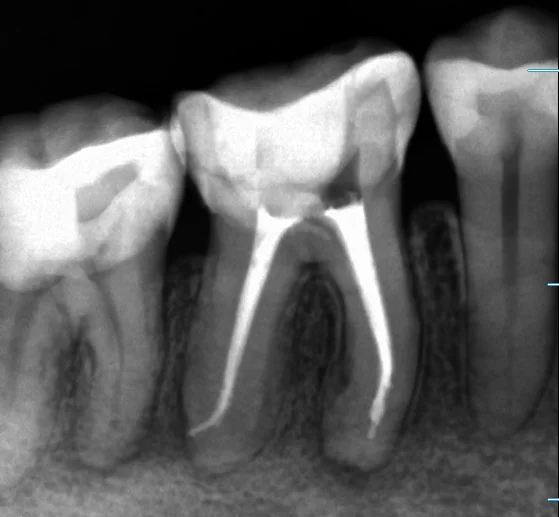

まずは術前です

「ほとんど全周」という広範囲に保険内の白い詰め物である「コンポジットレジン」が詰められています。 この治療は歯を削る量も少なくて済みますし、見た目も綺麗なのですが・・・

残念ながら今回は強度的に不可能なレベルを無理やり詰められてしまっていたようです。

詰められたコンポジットレジンが割れて中で大きく虫歯になっています。

そしてそのまま虫歯が神経に到達し根の先に膿が溜まってしまっているという状況です。

この赤丸で囲んでいる黒くなっているところが、骨が溶かされて膿が溜まっている状況の所です。